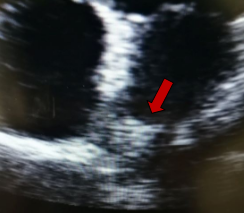

Γενικά, το διαθωρακικό υπερηχογράφημα (ακολουθείται σε μερικές περιπτώσεις από το διοισοφάγειο) είναι η πρώτη διαγνωστική εξέταση. Οι καρδιακοί όγκοι μπορεί να είναι ενδοκοιλοτικοί ή ενδομυοκαρδιακοί (ενδοτοιχωματικοί). Η ηχοκαρδιογραφία απεικονίζει τους ενδοκοιλοτικούς όγκους ως μία πυκνή υπερηχογενή μάζα ακίνητη με ευρεία βάση ή κινητή με μίσχο, που είναι προσαρτημένη στο ενδοκάρδιο. Αντίθετα, οι ενδοτοιχωματικοί όγκοι εμφανίζονται ως μία τοπική πάχυνση του μυοκαρδιακού τοιχώματος μίας κοιλίας. Οι καρδιακοί όγκοι μπορεί επίσης να προβάλλουν το περικάρδιο, με ή χωρίς συνύπαρξη περικαρδιακής συλλογής.

Στην ηχοκαρδιογραφία, το μύξωμα έχει την εμφάνιση μίας ανομοιογενούς κινητής μάζας, συχνά περίπου σφαιρικής, διαμέτρου συνήθως 4-8 cm, με λεία ή με λοβωτή (που φέρει μικρά τόξα στο περίγραμμά της) επιφάνεια. Η μάζα είναι προσαρτημένη στην ενδοκαρδιακή επιφάνεια (συνήθως στο μεσοκολπικό διάφραγμα) με στενή βάση, δηλαδή μίσχο. Σε κάποιες περιπτώσεις μπορεί να συνδέεται στο μεσοκολπικό διάφραγμα με ευρεία βάση. Η ηχογένεια τους δεν είναι ομοιογενής και μπορεί να περιλαμβάνουν υπόηχες περιοχές και σε κάποιες περιπτώσεις ασβεστώσεις. Τα πολυποειδή μυξώματα είναι μεγαλύτερα με λεία επιφάνεια και περιλαμβάνουν υπόηχες και κυστικές περιοχές λόγω εστιών αιμορραγίας και νέκρωσης εντός του όγκου . Τα θηλοειδή μυξώματα τείνουν να είναι μικρότερα και έχουν πολλαπλές λαχνοειδείς προσεκβολές. Αυτός ο υποτύπος σχετίζεται με εμβολικά φαινόμενα. Η θεραπεία ενός καρδιακού μυξώματος είναι η ριζική (πλήρης) χειρουργική αφαίρεση του όγκου.